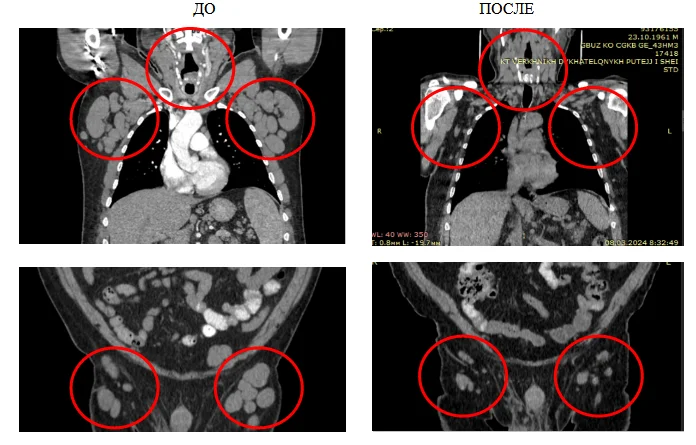

___Вот такими большими были лимфатические узлы у пациента перед началом лечения:

___Учитывая наличие показаний к началу лечения, наличие факторов неблагоприятного прогноза (делеция локуса гена ТР53/17р13), было принято решение – начать терапию, но не химиопрепаратами, а препаратом точечного (таргетного) воздействия. Выбран акалабрутиниб – один из самых современных препаратов – лечение которым проводят в такой ситуации и в нашей стране и во всем мире без исключения!

___И в мае 2023 года пациент начал лечиться. Ответ на лечение мы получили в течение месяца – нормализовался уровень лейкоцитов, уменьшились лимфоузлы.